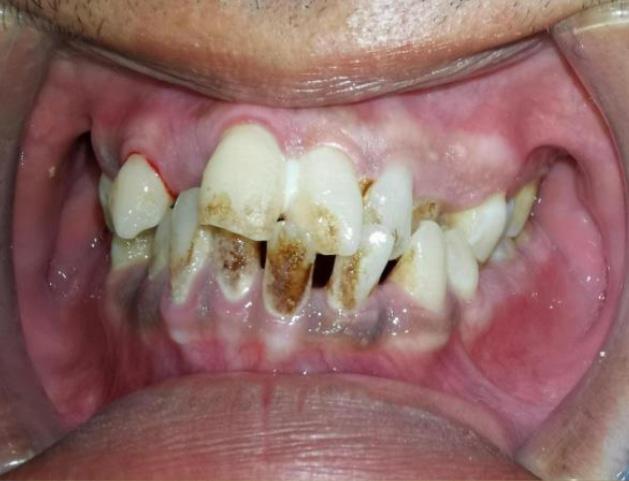

Apa itu rawatan penskaleran gigi?

Pernahkah anda ke mana-mana Pusat Pergigian Angkatan Tentera (PGAT) atau ke klinik pergigian di mana ramai doktor gigi menasihatkan anda untuk melakukan penskaleran gigi yang juga dikenali sebagai scaling? Penskaleran adalah prosedur menghilangkan tartar (plak yang mengeras) dan kotoran yang melekat pada gigi anda kesan daripada makanan, rokok atau teknik pemberusan yang kurang efektif. Rawatan ini adalah salah satu cara untuk mencegah dan merawat penyakit gusi jika doktor gigi telah mengesahkan anda mempunyai plak pada gigi.

Apa yang terjadi sewaktu rawatan penskaleran?

Jangan panik! Rawatan ini adalah termasuk rawatan rutin yang perlu dilakukan sekurang-kurangnya 2 kali setahun bagi mengelakkan penyakit gusi. Sepanjang

rawatan, doktor akan menggunakan ‘scaler’ untuk menghilangkan tartar dan kotoran pada gigi anda. Bagi yang tidak pernah melakukan rawatan ini akan merasa kurang selesa namun begitu, anda boleh mendapatkan rawatan ini bersama-sama ubat bius dari doktor gigi.

Apakah yang terjadi selepas rawatan penskaleran ini?

Anda akan merasa mulut dan gigi lebih bersih dan licin berbanding sebelum rawatan. Terdapat beberapa pesakit menyatakan mereka merasa lubang atau ruang di celah-celah gigi yang sebelum ini tidak pernah wujud akan terasa di ruang tersebut. Untuk pengetahuan umum, Tuhan telah menciptakan sesuatu sebaikbaik kejadian termasuklah ruang di antara gigi bagi memudahkan aliran air liur dan makanan. Air liur bukan sahaja bertugas sebagai ‘pelincir’ apabila kita makan, tetapi juga mempunyai sifat anti bakteria yang boleh mencuci dan membunuh kuman bahaya dalam mulut.

Oleh kerana makanan sering berada di celah-celah atau ruang di antara gigi, lama kelamaan makanan tersebut menjadi tartar dan tidak dapat dicuci menggunakan berus gigi biasa. Maka dengan itu, lama-kelamaan ruang tersebut tertutup dan anda akan merasakan tiada ruang dicelah permukaan gigi. Setelah rawatan penskaleran ini dilakukan, kesihatan gusi anda akan menjadi lebih baik dan anda akan merasakan tanda-tanda penyakit gusi seperti gusi mudah berdarah sewaktu memberus gigi akan berkurangan.

OLEH Maj (Dr) Tengku Natasha Eleena binti Tengku Ahmad Noor (801 RSAT Kem Penrissen)Apakah yang akan terjadi jika tidak melakukan rawatan penskaleran?

Tartar dan kekotoran pada gigi dan gusi anda akan menyebabkan keradangan pada gusi kerana lama kelamaan tartar akan berkumpul ke dalam gusi seterusnya merosakkan gusi dan tulang yang menyokong gigi anda. Mengikut American Academy of Periodontology, tanda-tanda anda mengalami penyakit gusi adalah:

• Gusi merah, bengkak atau sakit lain di dalam mulut anda.

• Pendarahan semasa memberus gigi, menggunakan flos atau makan makanan keras.

• Gusi menjadi surut dari gigi yang menyebabkan gigi kelihatan lebih panjang daripada sebelumnya.

• Gigi menjadi longgar atau goyang.

• Nanah di antara gusi dan gigi.

• Terdapat seperti luka di mulut.

• Nafas berbau yang berterusan.

• Perubahan pada gigi anda apabila anda menggigit.

• Perubahan pada kesesuaian gigi palsu jika anda memakainya.

Penyakit gusi adalah termasuk penyakit yang senyap dan kebanyakan pesakit tidak merasa sakit sehingga penyakit ini menjadi lebih rumit. Rawatan penskaleran amat penting dalam mencegah penyakit gusi. Namun begitu, penjagaan kesihatan pergigian di rumah juga penting seperti memberus gigi 2 minit 2 kali sehari dan mengamalkan penggunaan flos atau berus ‘interdental’ yang boleh didapati di mana-mana farmasi berdekatan.

Sebelum rawatan penskaleran Selepas rawatan penskaleran Keadaan gigi yang tidak pernah melakukan rawatan penskaleran. (A) menunjukkan tartar yang berkumpul pada gusi (B) gusi berwarna merah, bengkak dan lembut seperti span (C) gigi kelihatan lebih panjang dan bergoyang akibat penurunan gusi dan tulangLUMUT, 10 Oktober 2023 - Sambutan Hari